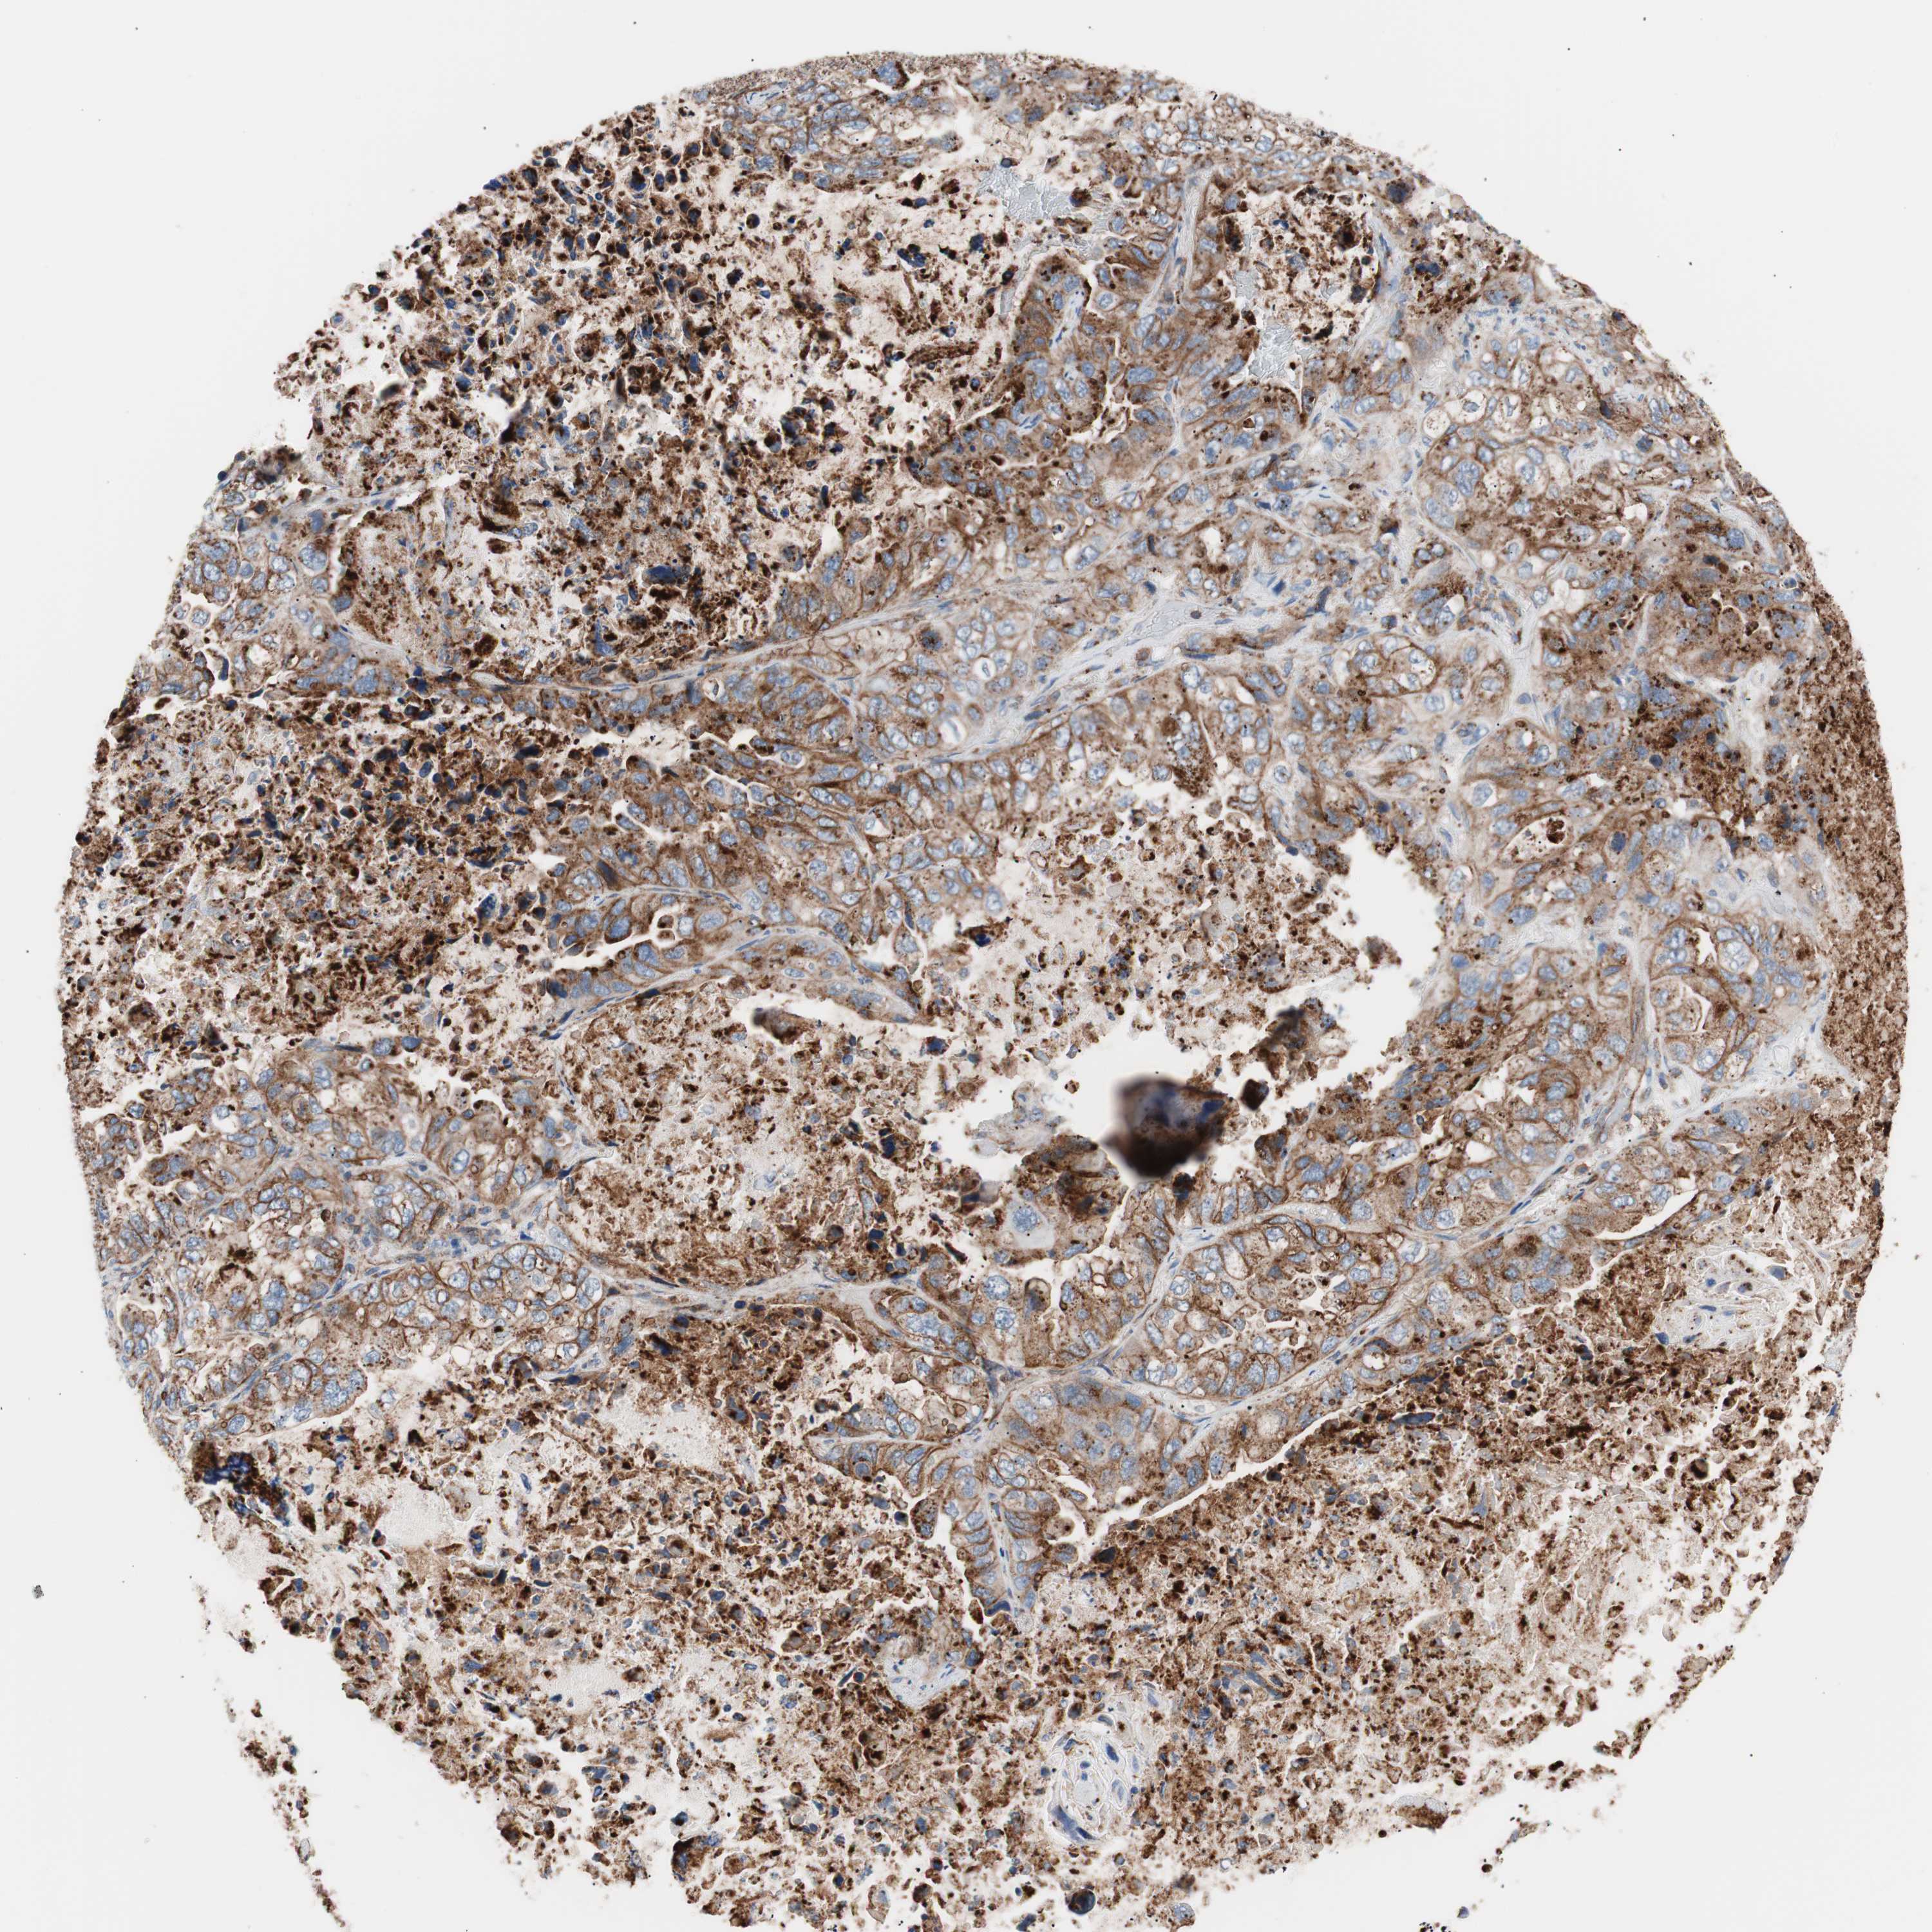

LUNG ADENOCARCINOMA (TCGA) - Interactive survival scatter ploti

The Survival Scatter plot shows the clinical status (i.e. dead or alive) for all individuals in the patient cohort, based on the same data that underlies the corresponding Kaplan-Meier plots. Patients that are alive at last time for follow-up are shown in blue and patients who have died during the study are shown in red.

The x-axis shows the expression levels (FPKM) of the investigated gene in the tumor tissue at the time of diagnosis. The y-axis shows the follow-up time after diagnosis (years). Both axes are complimented with kernel density curves demonstrating the data density over the axes. The top density plot shows the expression levels (FPKM) distribution among dead (red) and alive patients (blue). The right density plot shows the data density of the survived years of dead patients with high and low expression levels respectively, stratified using the cutoff indicated by the vertical dashed line through the Survival Scatter plot. This cutoff is automatically defined based on the FPKM cutoff that minimizes the p-score. The cutoff can be changed by dragging the vertical line or by entering a cutoff value in the square labeled "Current cut-off".

Under the Survival Scatter plot the p-score landscape (black curve; left axis) is shown together with dead median separation (red curve; right axis). Dead median separation is the difference in median mRNA expression between patients who have died with high and low expression, respectively. It is calculated as follows: median FPKM expression of dead patients with high expression - median FPKM expression of dead patients with low expression. This is intended to aid the user in visually exploring custom cutoffs and the associated p-scores and dead median separation.

Individual patient data is displayed and can be filtered by clicking on one or more of the category buttons on the top of the page. Categories describing expression level and patient information include: high, low, alive, dead, female, male and tumor stages. The scale of the x-axis can be toggled between linear and log-scale by clicking on the "x log" button. Mouse-over function shows TCGA ID, patient information and mRNA expression (FPKM) for each patient.

& Survival analysisi

Kaplan-Meier plots summarize results from analysis of correlation between mRNA expression level and patient survival. Patients were divided based on level of expression into one of the two groups "low" (under cut off) or "high" (over cut off). X-axis shows time for survival (years) and y-axis shows the probability of survival, where 1.0 corresponds to 100 percent.

FLOT2 is not prognostic in Lung Adenocarcinoma (TCGA)

: 70.38

: N/A

N/A

Average pTPM 74.7

Number of samples 497